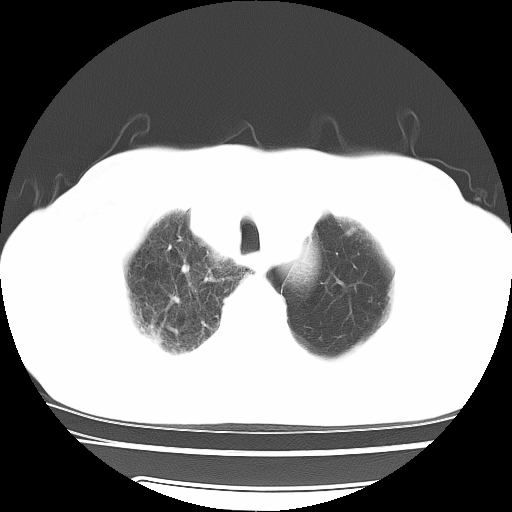

男,71岁,咳嗽,气喘10年,再发并咯血.胸片见气胸

考虑  左肺中心型肺癌伴阻塞性肺炎,肺不张,纵膈淋巴结肿大。慢支炎,肺气肿,左侧气胸肺压缩5%

左侧中央型肺癌伴纵膈淋巴结转移。

左肺中心型肺癌伴阻塞性肺炎,肺不张,纵膈淋巴结肿大

1)考虑左肺中心型肺癌伴阻塞性肺炎、左肺下叶肺不张、左侧肺气肿,纵膈淋巴结转移。2)左侧气胸(肺组织压缩约5%)。

左肺中心型肺癌伴阻塞性肺不张、肺气肿 。

1)考虑左肺中心型肺癌伴阻塞性肺炎、左肺下叶肺不张、左侧肺气肿,纵膈淋巴结转移。2)左侧气胸。